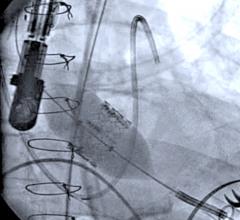

June 20, 2012 — Echocardiography is playing a key role in both the assessment and guidance of transcatheter aortic valve replacement (TAVR). Attendees at the American Society of Echocardiography’s 23rd Annual Scientific Sessions will have the opportunity to see this in action during a live TAVR procedure transmitted from Washington Hospital Center's hybrid cath lab.